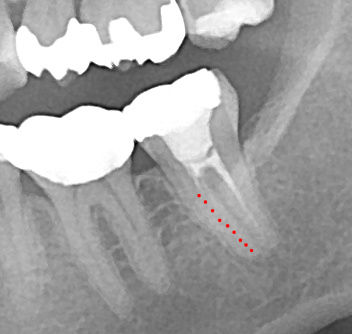

最初の時のレントゲンと比べてみるとわかりますが、近心根の赤い点線の部分が汚れていました。

今 現在 拡大 清掃中です

近心根のお薬を外して、中をきれいに拡大、清掃、消毒をしていきます。